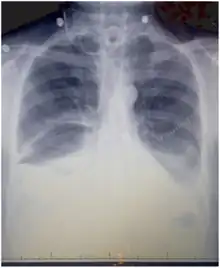

Chest X-rays can detect a chylothorax. It appears as a dense, homogeneous area that obscures the costophrenic and cardiophrenic angles. Ultrasounds can also detect a chylothorax, which appears as an echoic region that is isodense with no septation or loculation. However, neither a normal chest x-ray nor an ultrasound can differentiate a chylothorax from any other type of pleural effusion.[1]